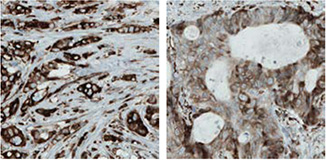

使用抗RBM3抗体HPA003624的IHC分析显示其在正常乳腺组织中的弱表达模式,但在乳腺癌组织中则呈分层模式(图1)。研究人员还进一步研究了其在较大乳腺癌队列中的表达,以及RBM3的表达显示出与延长的生存率相关5。

图 1.使用抗RBM3抗体(HPA003624)的免疫组化分析显示在正常乳腺组织中的弱表达(A)和差异表达,在肿瘤乳腺样品(B,C)中从弱到强的变化。